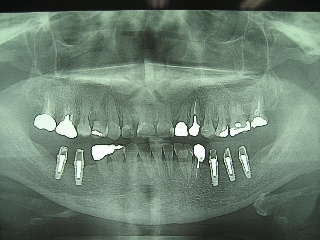

インプラント治療の為の矯正治療症例1

初診時年齢58歳。下顎臼歯部インプラント治療前の咬合改善を目的に来院。

咬み合わせを高くする事で受け口の改善ならびに下顎インプラント挿入スペースを作成した。

矯正治療と並行して専門医によるインプラント治療を行った。